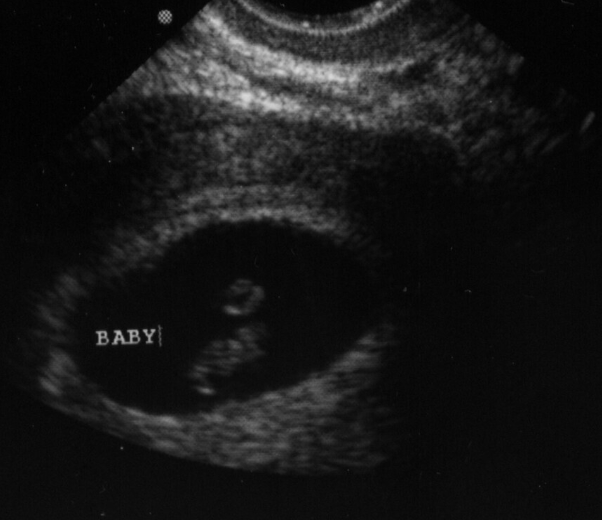

Pregnant patients often present to the Emergency Department in the first trimester with a variety of complaints, including vaginal bleeding, abdominal pain, and nausea/vomiting. The possibility of ectopic pregnancy in these patients is a major concern and should be ruled out. Emergency ultrasound can be used in the setting of pregnancy to evaluate for the presence or absence of intrauterine pregnancy. The images of Figure 22 demonstrate a gestational sac, the earliest finding of pregnancy by ultrasound, and the adjacent image shows a yolk sac, which is the minimum finding needed to confirm intrauterine pregnancy (IUP). A finding of intrauterine pregnancy (Video 2) in most patients effectively rules out ectopic (Video 3) or heterotopic pregnancy, which is the simultaneous presence of IUP and ectopic pregnancy (REF. 2 & 3).

![]() | ![]() |

Figure 22. Gestational sac seen on left, yolk sac present as ring within the gestational sac on the right image (Images courtesy of Matthew Lohse, MD. Baylor Scott & White-Temple).